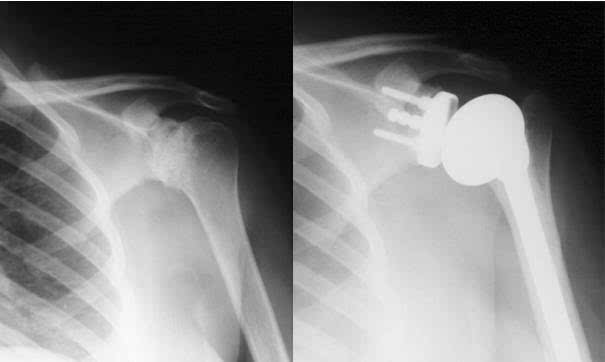

肩關節(jié)肩關節(jié)shoulderjoint由肩胛骨的關節(jié)盂和肱骨頭構成,屬球窩關節(jié)。

關節(jié)盂周緣有纖維軟骨環(huán)構成的盂緣附著,加深了關節(jié)窩。肱骨頭的關節(jié)面較大,關節(jié)盂的面積僅為關節(jié)頭的1/3或1/4,因此,肱骨頭的運動幅度較大。

因為肱骨頭較大,呈球形,關節(jié)盂淺而小,肩關節(jié)僅包繞肱骨頭的1/3,關節(jié)囊薄而松弛,所以肩關節(jié)是人體運動范圍最大而又最靈活的關節(jié),它可做前屈、后伸、內(nèi)收、外展、內(nèi)旋、外肩關節(jié)是由肩胛骨的關節(jié)盂與肱骨頭組成,故又叫肩肱關節(jié)。 因為肱骨頭較大,呈球形,關節(jié)盂淺而小,僅包繞肱骨頭的1/3,關節(jié)囊薄而松弛,所以肩關節(jié)是人體運動范圍最大而又最靈活的關節(jié),它可做前屈、后伸、內(nèi)收、外展、內(nèi)旋、外旋以及環(huán)轉等運動。

但肩關節(jié)的這個結構上的特點雖然保證了它的靈活性,但它的牢固穩(wěn)定性都較其他關節(jié)為差,是全身大關節(jié)中結構最不穩(wěn)固的關節(jié)。 最常見的是向肩關節(jié)的前下脫位,因為肩關節(jié)的上方有肩峰、喙突及連于其間的喙肩韌帶,可以防止肱骨頭向上脫位。

肩關節(jié)的前、后、上部都有肌肉、肌腱與關節(jié)囊纖維層愈合,增強了其牢固性。而只有關節(jié)囊的前下部沒有肌肉、肌腱的增強,這是肩關節(jié)的一個薄弱區(qū)。

因此當上肢外展時,在外力作用下或跌倒時,如上肢外展外旋后伸著地,肱骨頭可沖破關節(jié)囊前下方的薄弱區(qū),移出到肩胛骨的前方,造成肩關節(jié)前脫位。 這時患肩塌陷,失去圓形隆起的輪廓,形成所謂的“方肩”。